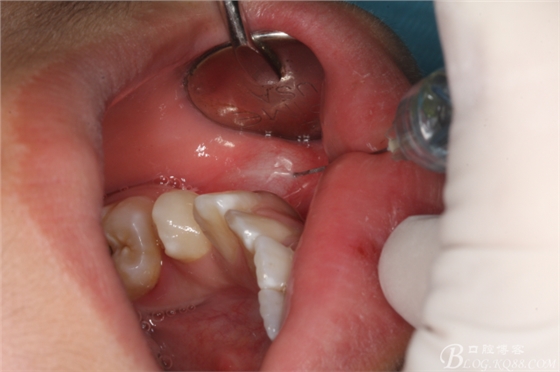

圖2.行左側(cè)下牙槽神經(jīng)阻滯麻醉加局部浸潤麻醉